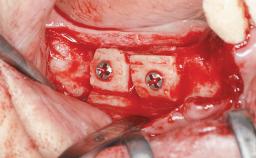

Le Fort I Interpositional Graft and Mandibular Sandwich Osteotomy for Maxillofacial Rehabilitation after Severe Periodontitis

Bone Augmentation Horizontal|Sinus Floor Elevation|Staged|Vertical

Augmentation Materials Autogenous chips|Autogenous block(s)|Xenogenous|Membrane

Bone Volume Deficient vertically or deficient vertically AND horizontally